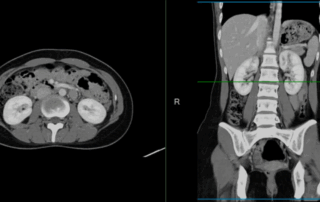

Can A CT Scan Detect Colon Cancer? Colon cancer is one of the deadliest forms [...]

A computed tomography (CT) scan is a diagnostic tool that allows medical professionals to [...]